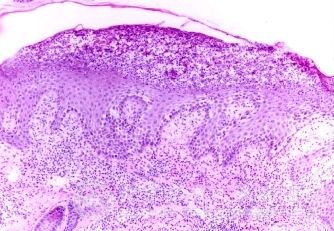

北京京城皮肤医院指出,药物皮炎需鉴别的疾病有:麻疹、猩红热:无用药史,全身中毒症状较明显、皮疹色泽不如药疹鲜艳,自觉不痒或轻痒,有各自固有体征,如猩红热有草莓舌及口周苍白圈。麻疹的颊粘膜可见科氏斑。